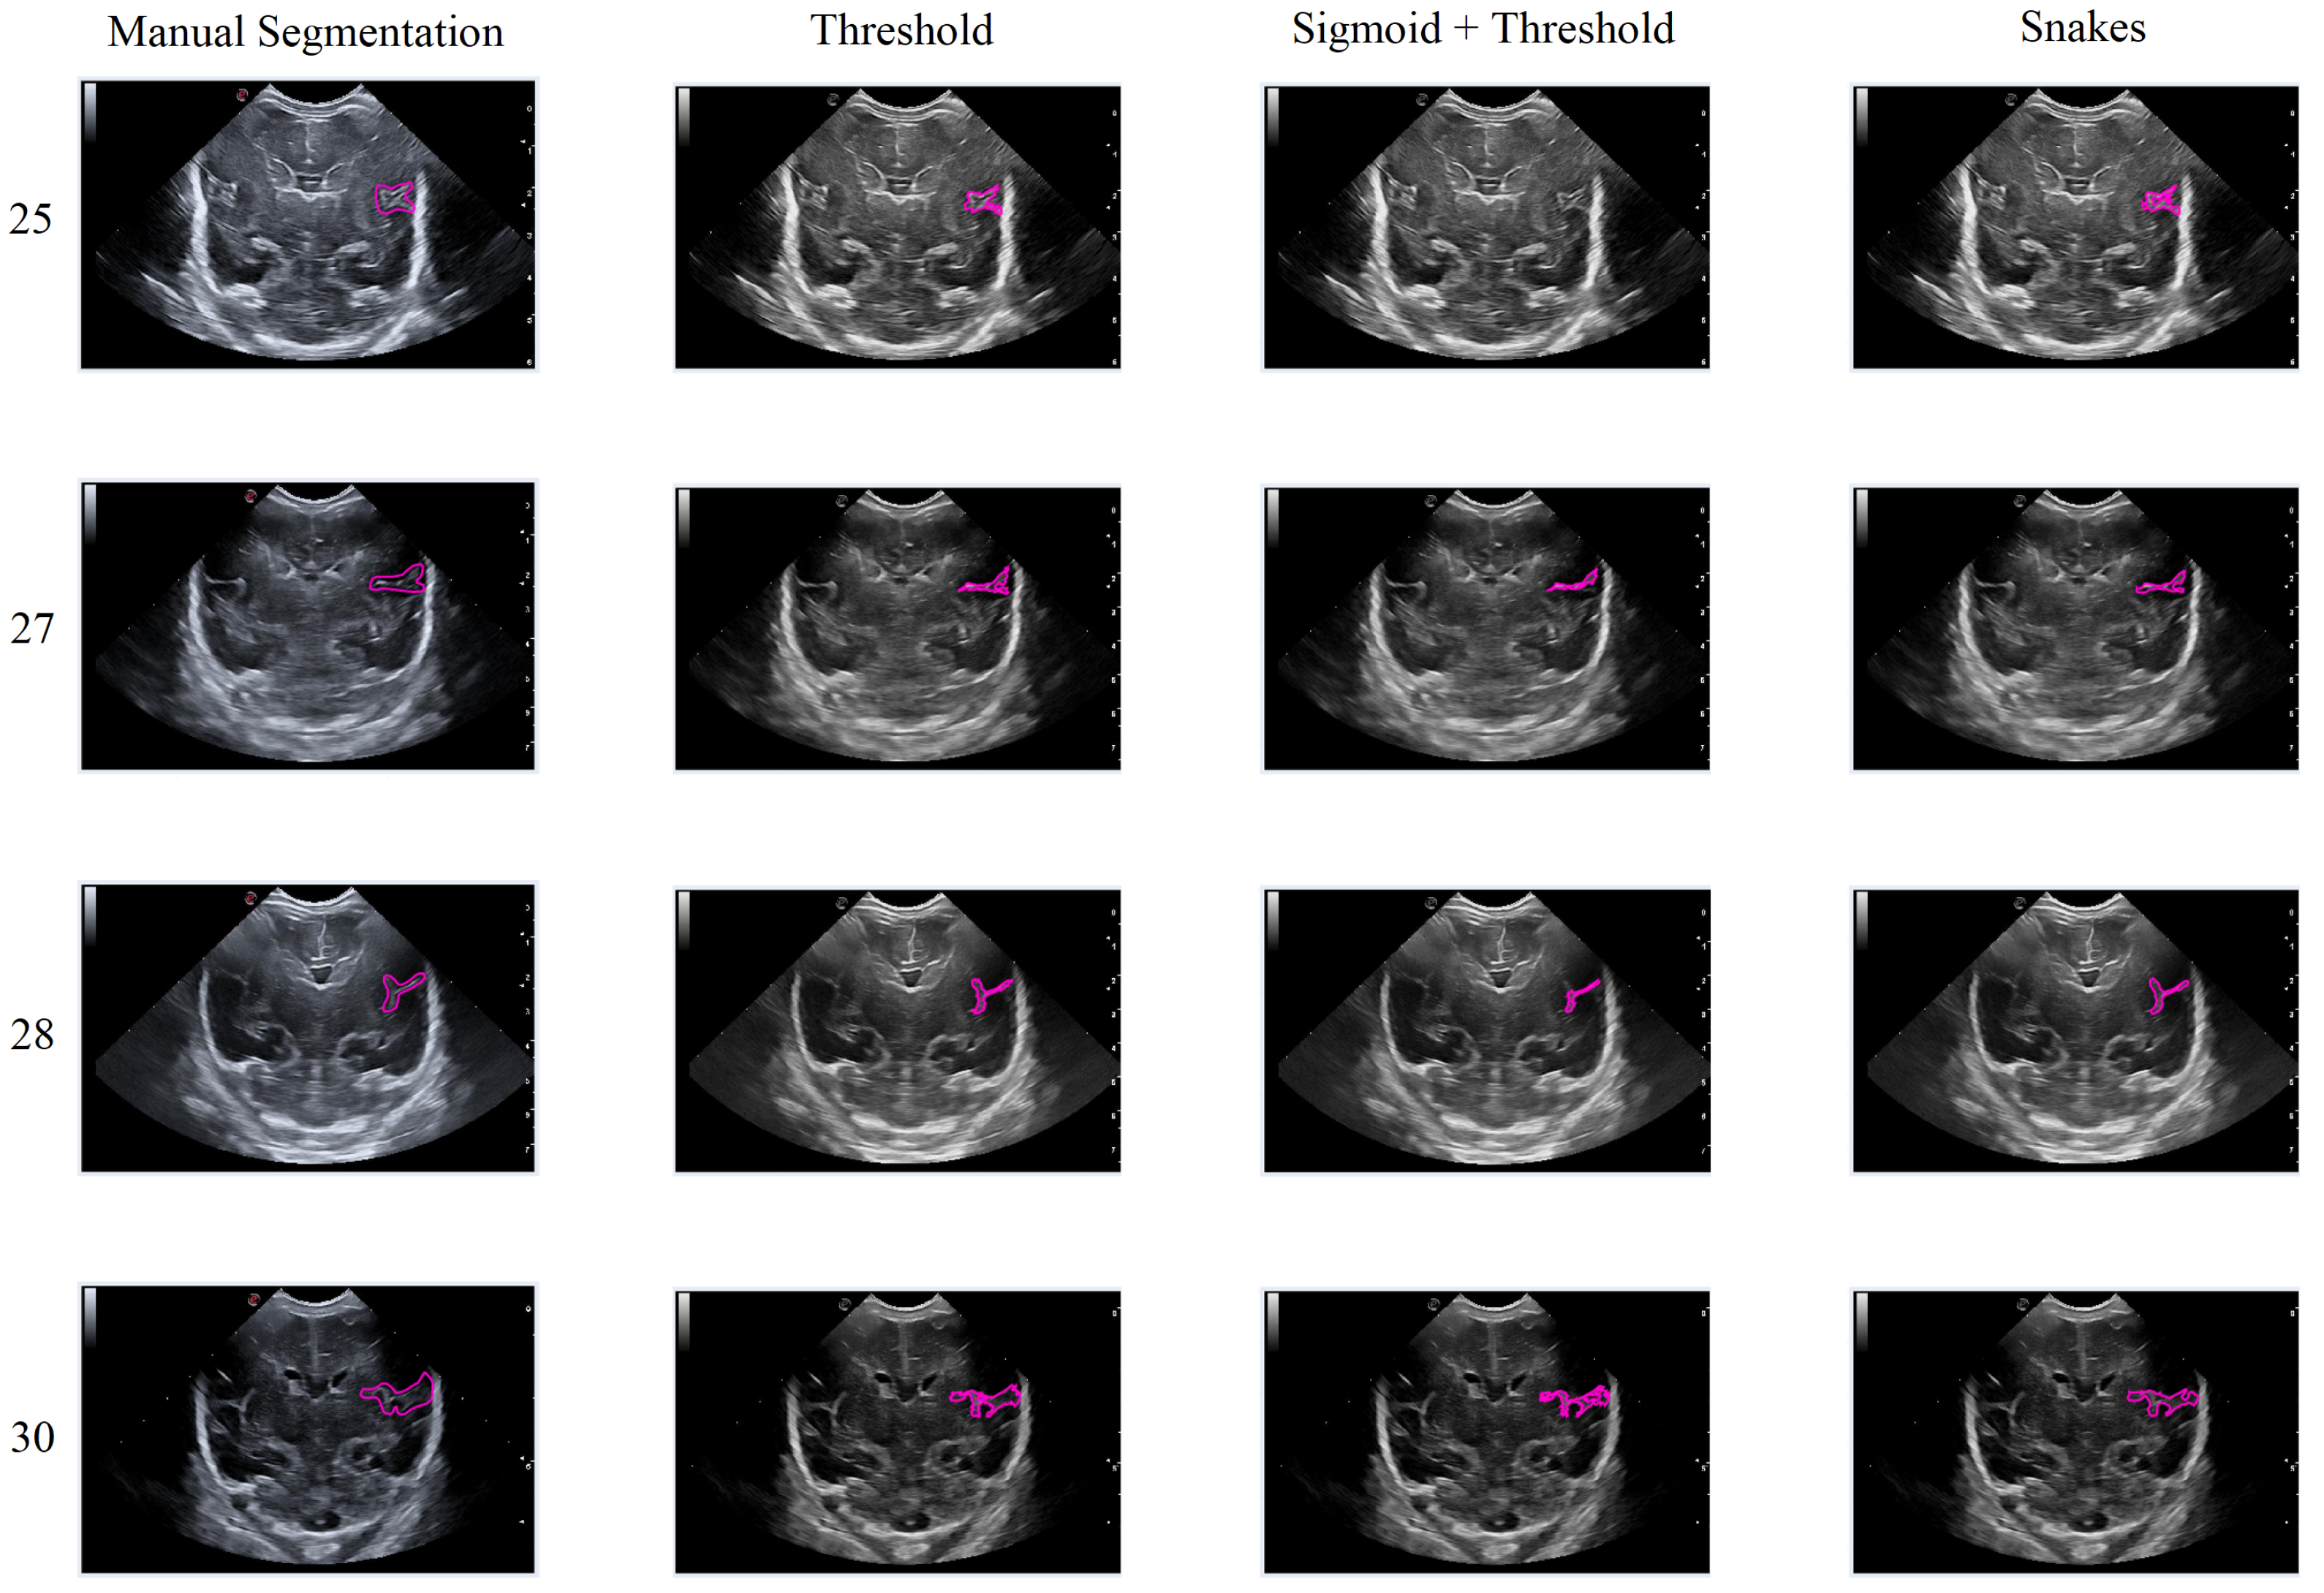

In this second scenario, we will analyze the segmentation results of the different methods applied to the Sylvian furrow at four different weeks of gestation (weeks 25, 27, 28, and 30) in various infants. Our aim here is to investigate how the noise present in ultrasound images affects the performance of the segmentation algorithms across different cases.

In the first row of Figure 17, it was observed that the Sigmoid + Threshold method failed to segment the groove, while the Threshold and Snakes methods were successful, but only if the groove was well defined. In the subsequent rows, which corresponded to weeks 27, 28, and 30 of gestation, a clear difference was observed between the methods that utilized the Threshold (Threshold and Sigmoid + Threshold). The Sigmoid + Threshold method was found to be more sensitive and faithful in segmenting the furrow, but lost precision when defining its shape. On the other hand, the Threshold method lost precision during segmentation but improved the definition of the furrow’s shape.

Another notable observation from the figure is the difference in the way the methods perform segmentation. Specifically, the Snake method produces smoother segmentation results, which appear to be more regular and follow the shape of the groove more accurately. In contrast, when the Threshold method is applied, the segmentation result is more irregular and abrupt, with small peaks visible in the defined shape of the groove. It is evident that in some instances where the groove is more affected by noise, particularly during weeks 27 and 28, the Sigmoid preprocessing can lead to the loss of information about the groove’s shape, resulting in a failure to segment part of it using this method.

Figure 17. Segmentation of the Sylvian sulcus applying the three defined segmentation methods (Threshold, Sigmoid + Threshold, and Snakes) for different babies and weeks.